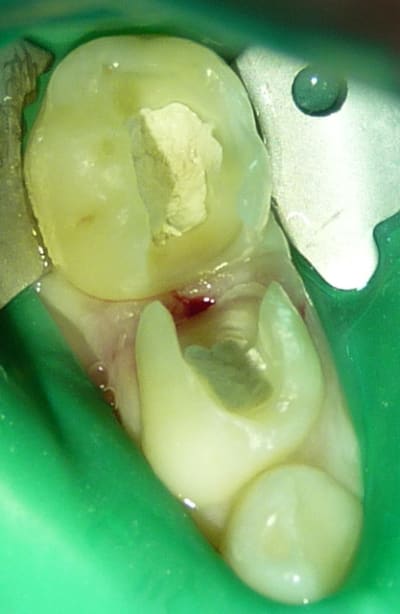

Ci-dessous, le mieux que j'arrive à faire avec mon "vieux" bridge.